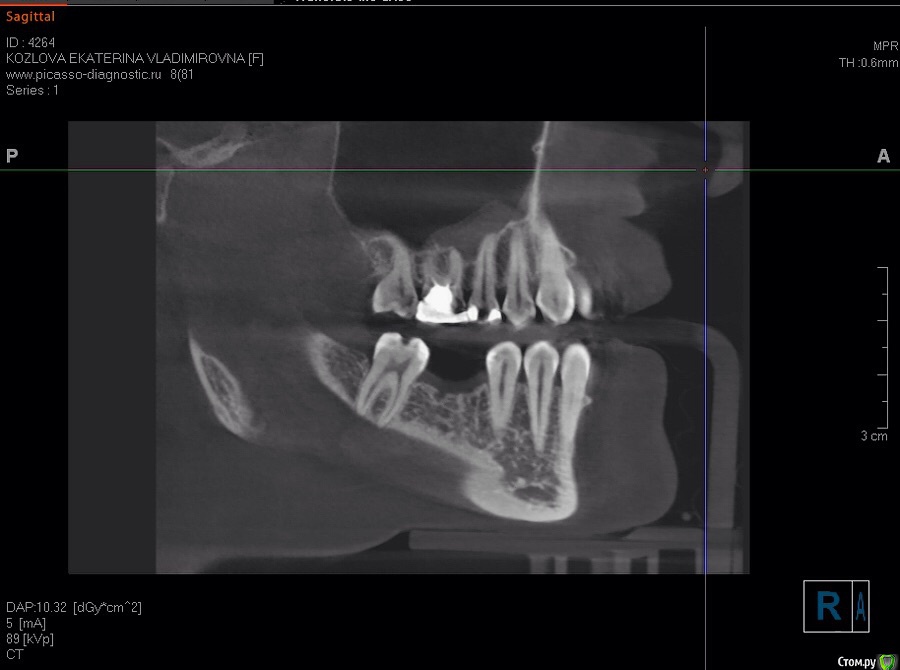

katrin12098 Опубликовано 15 августа, 2015 Поделиться Опубликовано 15 августа, 2015 (изменено) Здравствуйте!Подскажите пожалуйста.Заболела верхняя пятерка,пошла на прием к стоматологу сделали снимок сказали киста и нужно удалять в стационаре,так как зуб находиться рядом с гайморовой пазухой в поликлинике удалять отказались. Пропила пять дней амоксиклав зуб перестал беспокоить, насколько велика вероятность перфорации гайморовой пазухи и возможно ли удалить в клинике или всё же лучше обратиться в больницу в челюстно лицевую хирургию и удалить там? и какие могут быть осложнения? и возможно ли сохранить зуб? Изменено 15 августа, 2015 пользователем katrin12098 Ссылка на комментарий

katrin12098 Опубликовано 16 августа, 2015 Автор Поделиться Опубликовано 16 августа, 2015 Ходила на консультацию к двум хирургам и к члх в нии лор без лишних объяснений и разговоров сказали удалять(в меди сказали что нужно сделать кт пятого и шестого и после этого только возможно подумать над лечением..после удаления нижнего шестого с той же кистой паника и страх., Ссылка на комментарий

St. Опубликовано 16 августа, 2015 Поделиться Опубликовано 16 августа, 2015 Верхние пятый и шестой можно попробовать перелечить каналы и наблюдать. Если там нет трещин большая вероятность, что воспаление после качественной эндодонтии пройдет.Верхний шестой справа и центральный резец справа тоже необходимо перелечить каналы. И подумать о имплантации в области отсутствующего на нижней челюсти. Ссылка на комментарий

katrin12098 Опубликовано 19 августа, 2015 Автор Поделиться Опубликовано 19 августа, 2015 (изменено) Верхнюю пятерку решила удалять.подскажите что делать с шестым верхним?также интересует правая сторона пятый и шестой верхний зуб.возможна ли имплантация шестого нижнего и нужен ли костный блок? Изменено 19 августа, 2015 пользователем katrin12098 Ссылка на комментарий